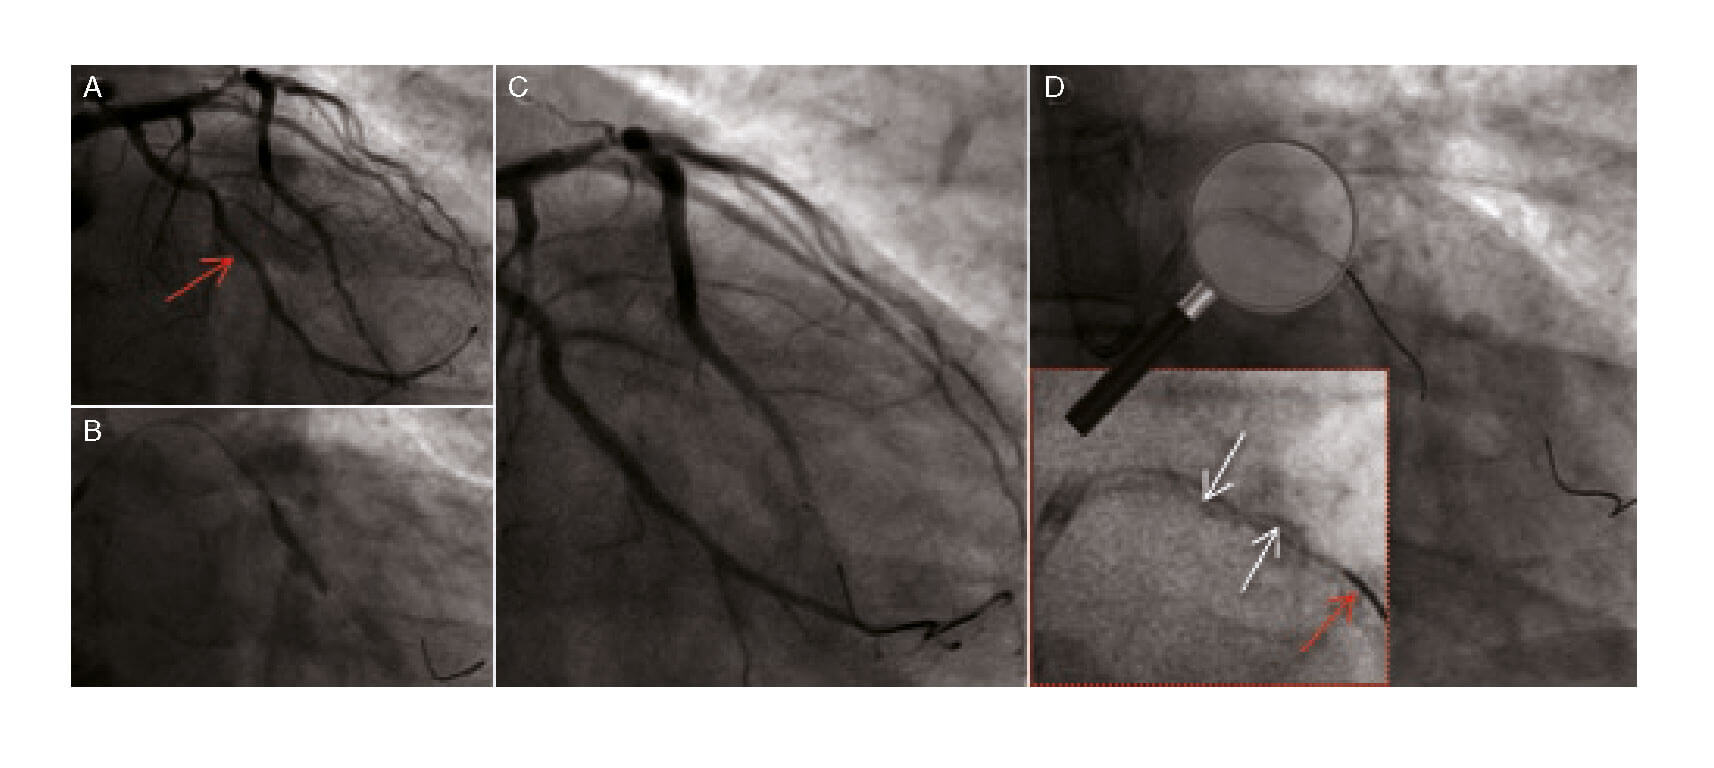

Varón de 72 años que, tras sufrir un infarto agudo de miocardio sin elevación del segmento ST (IAMSEST), es sometido a intervención coronaria percutánea (ICP) en etapas por presentar estenosis significativa de las arterias descendente anterior (DA) media y circunfleja (Cx) media (figura 1A; flecha roja). Después de colocar una guía intracoronaria hidrofílica y de alto torque en la Cx, se implantó sin complicaciones un stent farmacoactivo (SFA) (figura 1B y figura 1C). Sin embargo, a continuación no se logró extraer la guía, probablemente por atrapamiento en placa calcificada. La mayor tracción ejercida provocó la fractura parcial de la guía con deshilachamiento de los coils (figura 1D, flechas blancas; la flecha roja apunta a la segunda guía insertada). Se intentó recuperarla sin éxito empleando diferentes técnicas, como la extracción mediante lazo y la de la guía retorcida o trenzada (twisting wires) (vídeo 1 del material adicional).

Figura 1